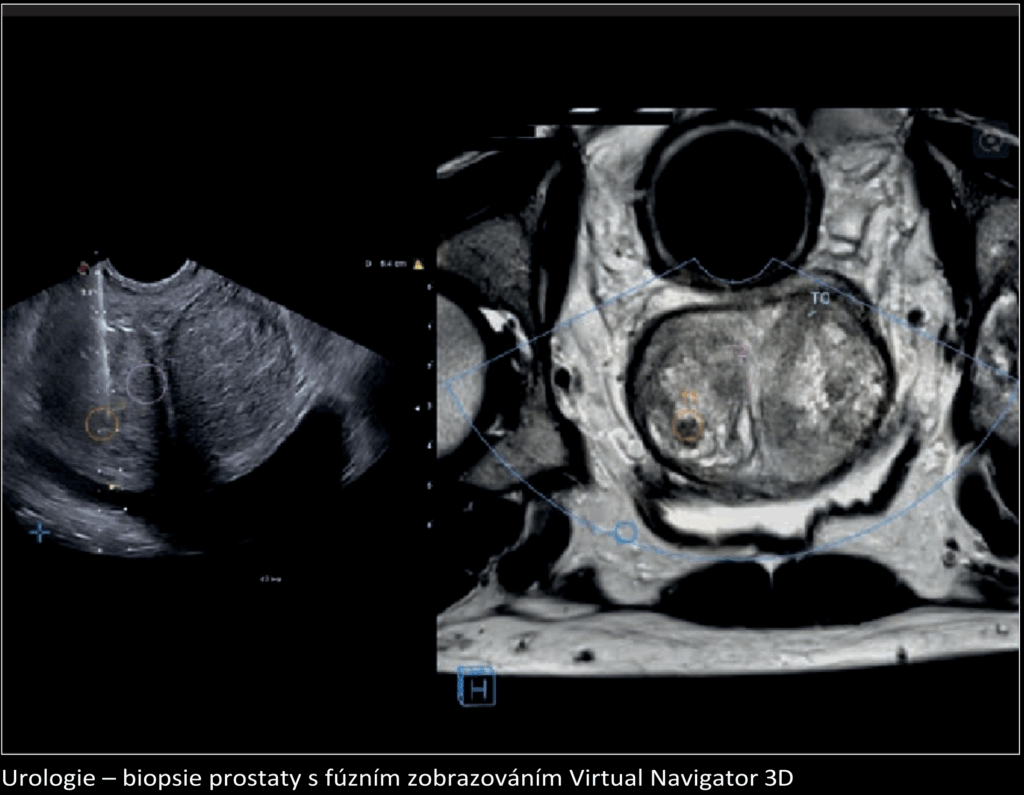

MyLab™ X8 eXP umožňuje propojení s nejmodernějšími systémy a doplňky pro snadnější sdílení dat a efektivnější diagnostiku.

Podporuje standardy DICOM, IHE compliance a wireless connectivity.

Díky kompatibilitě s doplňky, jako jsou MyLab™Desk evo, multi-modality archives, MyLab™Tablet, MyLabRemote a eStreaming, lze systém snadno přizpůsobit individuálním potřebám pracoviště.